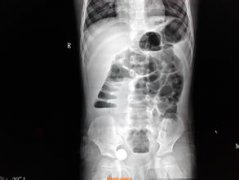

腸梗阻 是指任何原因引起的腸道通過(guò)障礙,而導(dǎo)致腸道和全身的病理變化。腸梗阻是小兒時(shí)期比較常見(jiàn)的急腹癥。 腸梗阻分類(lèi) 腸梗阻大致可分為機(jī)械性(器質(zhì)性)和動(dòng)力性(功能性)兩大類(lèi)。 機(jī)械...

腸梗阻 是指任何原因引起的腸道通過(guò)障礙,而導(dǎo)致腸道和全身的...